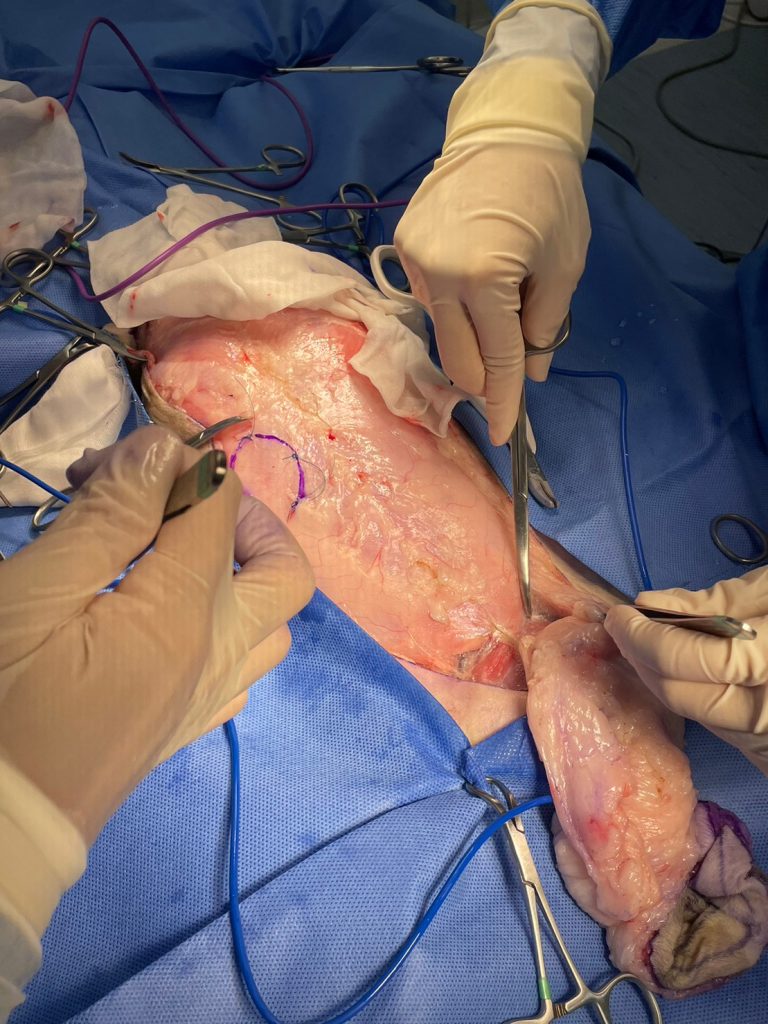

我們兩位外科醫師在確認Kulo的皮膚張力可以承受後,以極佳的默契順利的完成雙側全乳腺切除,而腫瘤區則多切一層腹壁肌肉。

我們隨即開始手術。

這張是手術後第24小時的照片,在良好止痛的幫助下,Kulo恢復得很順利。